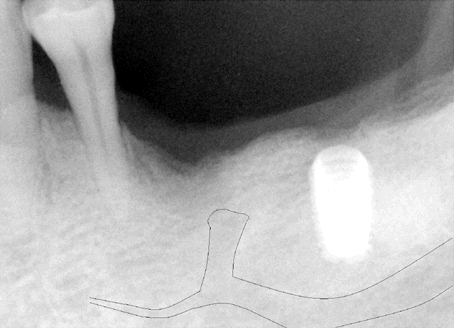

Fig.12 and 13 Since the surgeon failed to notice the relationship of initial osteotomy to the mental nerve, he kept increasing osteotomy depth (to ~11 mm below the alveolar ridge) and diameter to 4.5 mm for #20 and 5.0 mm for #19. After the patient left, he reviewed post-op X-ray and noticed that #20 implant pinched the inferior alveolar nerve (Fig.11). Tracing further shows that the implant overlaps the mental nerve (Fig.12). Paresthesia was found in the left lower lip and teeth. The extent of parethesia of the lip and chin was recorded. The offending implant was removed on the 3rd day post-op. Paresthesia decreased 4 weeks later and completely resolved by 2 months. Another 4 months later, the patient returned for #20 implant placement for the second time. A new pre-op PA was taken again immediately before the scheduled surgery. The high position of the mental nerve appears to wake up the doctor for the first time. The alternative (extracting #21, placing an implant on #21, using both #19 and 21 implants as abutments for fixed work) was proposed again. The patient did not accept it. The surgery was canceled. Since #19 implant was placed relatively too distally, it would be inappropriate to use to use it to make a cantilever fixed prosthesis. An implant should be placed in the narrow space between the mental nerve and #21 root (Fig.7). The angulation was designed in Fig. 3 and 5. Surgical stent was fabricated after placing orientation rod and tube (Fig.5) before cone beam. |

Fig. 14 and 15 Cone beam confirms the close relationship between the mental nerve and the root of the tooth #21. S: stent with barium sulfate for #20 implant placement; T: tube inside acrylic without barium sulfate for previous placement of #19 implant. Please note that as the mental nerve loops ascends, it is more buccally located. It is more likely to injury the mental nerve as osteotomy goes deep. Osteotomy tends to be in the middle of the bone. It is imperative to tilt the osteotomy as shown by simulation of implant placement (black rectangle in Fig.15). The osteotomy should also avoid injuring the incisive nerve (brown lines). Although cone beam provides tremendous information, the operator depends heavily upon routine X-ray during implant placement. He needs several quality intra-op X-ray to adjust the angulation and position of the osteotomy as shown below. |